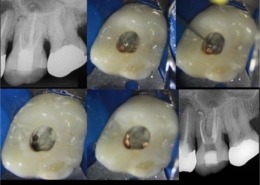

Tehnike pronalaska sekundarnog meziobukalnog kanala

Oblik obrisa pristupnog kaviteta prvog gornjeg kutnjaka trokutast je i smješten u mezijalnoj polovici zuba s osnovom prema bukalno i vrhom prema lingvalno (Slika 3.). Meziobukalni korijen vrlo je širok u bukolingvalnom smjeru, tako da je česta pojava manjeg sekundarnog meziobukalnog kanala. [8] Dno pulpne komore ima određena morfološka obilježja koja su od velike pomoći pri traženju kanala. Obično su na dnu vidljive linije koje vode prema ulazima u kanale i tvore zamišljenu „mapu“, odnosno rostrum canalis. [1] Primarni meziobukalni kanal smješten je blago distalno u odnosu na vrh meziobukalne kvržice, dok je manji sekundarni meziobukalni kanal smješten mezijalno od zamišljene linije koja povezuje primarni meziobukalni i palatinalni kanal, približno na udaljenosti 1 do 3 mm od primarnog. [4] Sam ulaz u sekundarni meziobukalni kanal teško je uočljiv kliničkom inspekcijom zbog dentinskog ramena koje ga pokriva i koje je potrebno ukloniti za lakši pristup kanalu. Osim dentinskog ramena, problem je i meziobukalni nagib ulaza te nagla zavijenost kanala u koronarnoj trećini prema mezijalno što ukazuje na najjednostavniji pristup iz distopalatinalnog kuta. [10] Upravo iz navedenih razloga, kako bi se poboljšala sama pristupačnost kanalu, potrebna je početna priprema i modifikacija pristupnog kaviteta u romboidni oblik uz oprez i minimalnu invazivnost. Istraživanjem je dokazano da je uklanjanje dentina s dna pulpne komore (tzv. troughing) do 2 mm od palatinalnog prema primarnom meziobukalnom kanalu korisna metoda te da su njezine prednosti nadmašile rizik od perforacije. [1] Potrebna je i dobra vizualizacija dna pulpne komore za što se koristi mikroskop, lupe ili barem intraoralno ogledalo s prednjom reflektirajućom površinom. Uz dobru pristupačnost i vizualizaciju lakše je istraživanje dna pulpne komore i traženje ulaza u kanal. Instrumenti poput DG16 Explorer (Slika 4.) ili tanki instrument poput D finder #10 (Slika 5.) od velikog su značaja za lociranje kanala. Iznimno su korisni i ultrazvučni instrumenti koji selektivno uklanjaju kalcifikacije u pulpi i čuvaju dentin od pretjerane štete te otkrivaju skriveni ulaz u kanal. Važno ih je pažljivo koristiti, laganim, kontroliranim pokretima kako bi se izbjeglo pretjerano uklanjanje dentina i iatrogena perforacija. Kod samog traženja kanala, irigacija može pomoći u njihovoj lokalizaciji. Natrijev hipoklorit ima antimikrobna svojstva, osigurava bolju vidljivost, smanjuje rizik od kontaminacije, omogućuje lakši pristup instrumentima te uklanja ostatke organskog materijala. Pulpni ostaci mogu reagirati s natrijevim hipokloritom pri čemu se stvaraju mjehurići, odnosno dolazi do stvaranja kisika, što je pokazatelj položaja ulaza u kanal te potencijalnog postojanja novih, neotkrivenih kanala. Uz natrijev hipoklorit, kao dijagnostičko sredstvo za lociranje kanala upotrebljava se i kemijski spoj 1% natrijev fluorescein. To je oftalmološka otopina koja ima svojstvo vezanja za vezivno tkivo i svijetli kada se izloži plavom svjetlu. Nalapatti i Glassmann predložili su njegovu upotrebu, na način da se otopina aplicira u pulpnu komoru i ostavi da djeluje i reagira 2 minute. [1] Aplikaciju je potrebno obaviti oprezno i paziti na određeni vremenski interval djelovanja, budući da postoji rizik od obojenja zuba. Nakon toga potrebno ju je izložiti plavom polimerizacijskom svjetlu, a kanale promatrati mikroskopom. Važno je obilno isprati pulpnu komoru natrijevim hipokloritom nakon završenog postupka. Na temelju te tehnike, napravljen je i veliki pomak u razvitku mikroskopa, odnosno kobaltno-plavog filtra koji omogućuje još precizniju i jednostavniju primjenu natrijevog fluoresceina. [1] Još jedan vrijedan dijagnostički alat, koji nam omogućuje trodimenzionalan prikaz anatomije jest CBCT (konusna kompjutorizirana tomografija). Ova tehnologija omogućuje bolju vizualizaciju, prepoznavanje varijacija, planiranje samog pristupa, minimalno invazivnu preparaciju te veću predvidivost terapije (Slika 6.). Kliničkom studijom dokazano je da je učinkovitost korištenja CBCT-a u pronalaženju dodatnih sekundarnih meziobukalnih kanala u maksilarnim kutnjacima ograničena te je sam kanal bio prikazan u 33 % slučajeva. [11]

Instrumentacija kanala

Budući da meziobukalni primarni i sekundarni kanal često pripadaju tipu II konfiguracije prema Vertucciju te da postoji varijabilnost položaja kanala, nameću se specifični zahtjevi njihove obrade. Upravo zato se klinički smatra racionalnim i tehnički opravdanim u potpunosti instrumentirati i oblikovati MB1 kanal prije početka instrumentacije MB2. Obrada kanala često predstavlja izazov zbog izrazite mezijalne zakrivljenosti u koronarnom dijelu kanala. Nakon lokalizacije ulaza prvi korak je sondiranje kanala malim ručnim instrumentima veličine ISO #08–#10. U ovom koraku nije nužno dosegnuti vanjski otvor kanala. Za širenje ulaza u korijenske kanale korisni su nikal titanski rotacijski instrumenti za proširenje ulaza u kanal (eng. orifice opener) koji se primjenjuju u blagim kretnjama iščetkavanja, usmjerenim od furkacije (Slika 7.). Takav pristup stavlja naglasak na očuvanje strukturnog integriteta korijena, jer omogućuje selektivno uklanjanje dentina bez nepotrebnog slabljenja stijenki kanala u „opasnoj zoni ”. Opasne zone su zabilježena područja korijenskih stijenki gdje je dentin, u prosjeku, značajno tanji, što povećava predispoziciju za nastanak mehaničkih uzdužnih perforacija (eng. strip perforation) tijekom agresivne obrade. Korisno je znati da je debljina dentina mezijalnog korijena u području prema furkaciji, tj. na distalnoj stijenci MB2 kanala, u približno 77 % slučajeva manja je od 1 mm. [12] Nakon toga se radi predinstrumentacija ručnim instrumentima veličine ISO #15–#20 ili strojnim instrumentima kako bi se uspostavila sigurna radna putanja (eng. glide path). U starijih pacijenata ili kod zuba s opsežnim restauracijama, MB2 kanal često bude kalcificiran, što značajno otežava instrumentaciju. U takvim slučajevima preporučuje se kombinacija rigidnijeg ručnog instrumenta sa 17 % EDTA otopinom. [13] Balanced force tehnika instrumentacije prikladna je za zakrivljene i uske kanale jer omogućuje očuvanje originalne putanje, smanjenje torzijskog stresa instrumenta i očuvanje strukturalnog integriteta korijena. Ona predstavlja sustavan pristup ručnoj instrumentaciji zakrivljenih kanala, temeljen na izmjeničnim rotacijama instrumenta i preciznom pritisku operatora. Ručni se instrument inicijalno uvodi u kanal i okreće u smjeru kazaljke na satu, čime se njegove režuće površine utiskuju u dentin. U ovoj fazi koriste se K-fleksibilni (K-Flex) instrumenti koji su zbog svoje elastičnosti i specifičnog dizajna pogodni za ovu tehniku. Ovaj početni korak omogućuje kontrolirano pomicanje instrumenta prema apikalno pri čemu spiralni raspored žljebova i progresivni konus potiskuju režuće bridove dublje u stijenke kanala, stvarajući stabilnu radnu putanju. Operator osjeća silu potrebnu za zahvaćanje dentina, što pruža taktilnu povratnu informaciju o napredovanju instrumenta. Nakon toga, instrument se rotira suprotno od kazaljke na satu, dok operator primjenjuje lagani pritisak prema apikalno. Kada tlak premaši sile smicanja dentina, dolazi do kontroliranog rezanja, što omogućuje preciznu kontrolu svakog reznog koraka. Od drugih, često korištenih tehnika ručne instrumentacije, valja spomenuti i crown-down tehniku koja se, po mnogo čemu, pokazala superiornijom od klasične step-back tehnike kada su u pitanju uski korijenski kanali s kutom zakrivljenosti od 10 do 35 stupnjeva. Shodno tomu, izvrsne rezultate pokazuje hibridna tehnika, koja objedinjuje prednosti obje metode. Klinički protokol započinje instrumentacijom koronarne trećine crown-down tehnikom čime otvaramo liniju pristupa za dublje dijelove. Potom slijedi instrumentacija apikalne trećine, te se konačno uniformno proširenje kanala postiže step-back tehnikom u srednjoj trećini. Kod odabira strojnih instrumenata treba imati na umu termičke fazne transformacije NiTi legura te odabrati sustav koji omogućuje iznimnu fleksibilnost i precizno praćenje prirodnih zakrivljenosti kanala, što je karakteristika sustava s dominantno martenzitnom fazom. Primjerice, Protaper Next pokazuje visoku otpornost na ciklički zamor u zakrivljenim kanalima zahvaljujući kombinaciji M-Wire legure i varijabilnog konusa instrumenta (Slika 8.). [14] Takva svojstva omogućuju sigurno vođenje instrumenta kao i očuvanje originalnog oblika kanala i integriteta stijenki. Preporuka je da se širenje kanala ograniči na instrument #25, jer istraživanja pokazuju da instrumenti #30 ili veći značajno smanjuju debljinu preostale distalne stijenke MB2 kanala na manje od 0,3 mm. [12] Takva debljina smatra se kritičnom za podnošenje sila koje nastaju tijekom lateralne kondenzacije gutaperke, a istovremeno povećava rizik od vertikalne frakture korijena. Vrlo uspješne kliničke rezultate pokazuje TruNatomy od Maillefera koji je specifično kreiran kako bi se optimizirala instrumentacija uskih i zavijenih kanala. Ekscentrični dizajn smanjuje lokalno naprezanje instrumenta te reducira torzijski stres, a gracilniji, “slim” dizajn i regresivni konus omogućuju očuvanje tvrdog zubnog tkiva u cervikalnom dijelu (Slika 9.). [15] S druge strane, nakon pažljive ručne instrumentacije i formiranja sigurne radne putanje, moguće je koristiti Reciproc sustav, načinjen od M-Wire legure, a koji omogućuje obradu kanala sa samo jednim instrumentom, tzv. “single file” koncept. Ovaj sustav primjenjuje reciprocirajuću kinematiku s rotacijom od 150 stupnjeva u smjeru suprotnom od kazaljke na satu i 30 stupnjeva u smjeru kazaljke na satu. Međutim, zbog velike koničnosti standardnih Reciproc instrumenata, danas je na tržištu dostupna novija varijanta, sustav Reciproc Minima, koji je zahvaljujući gracilnijem dizajnu i naprednijoj leguri prikladniji za obradu MB2, osobito u kombinaciji s prethodnim ručnim širenjem kanala. [14]